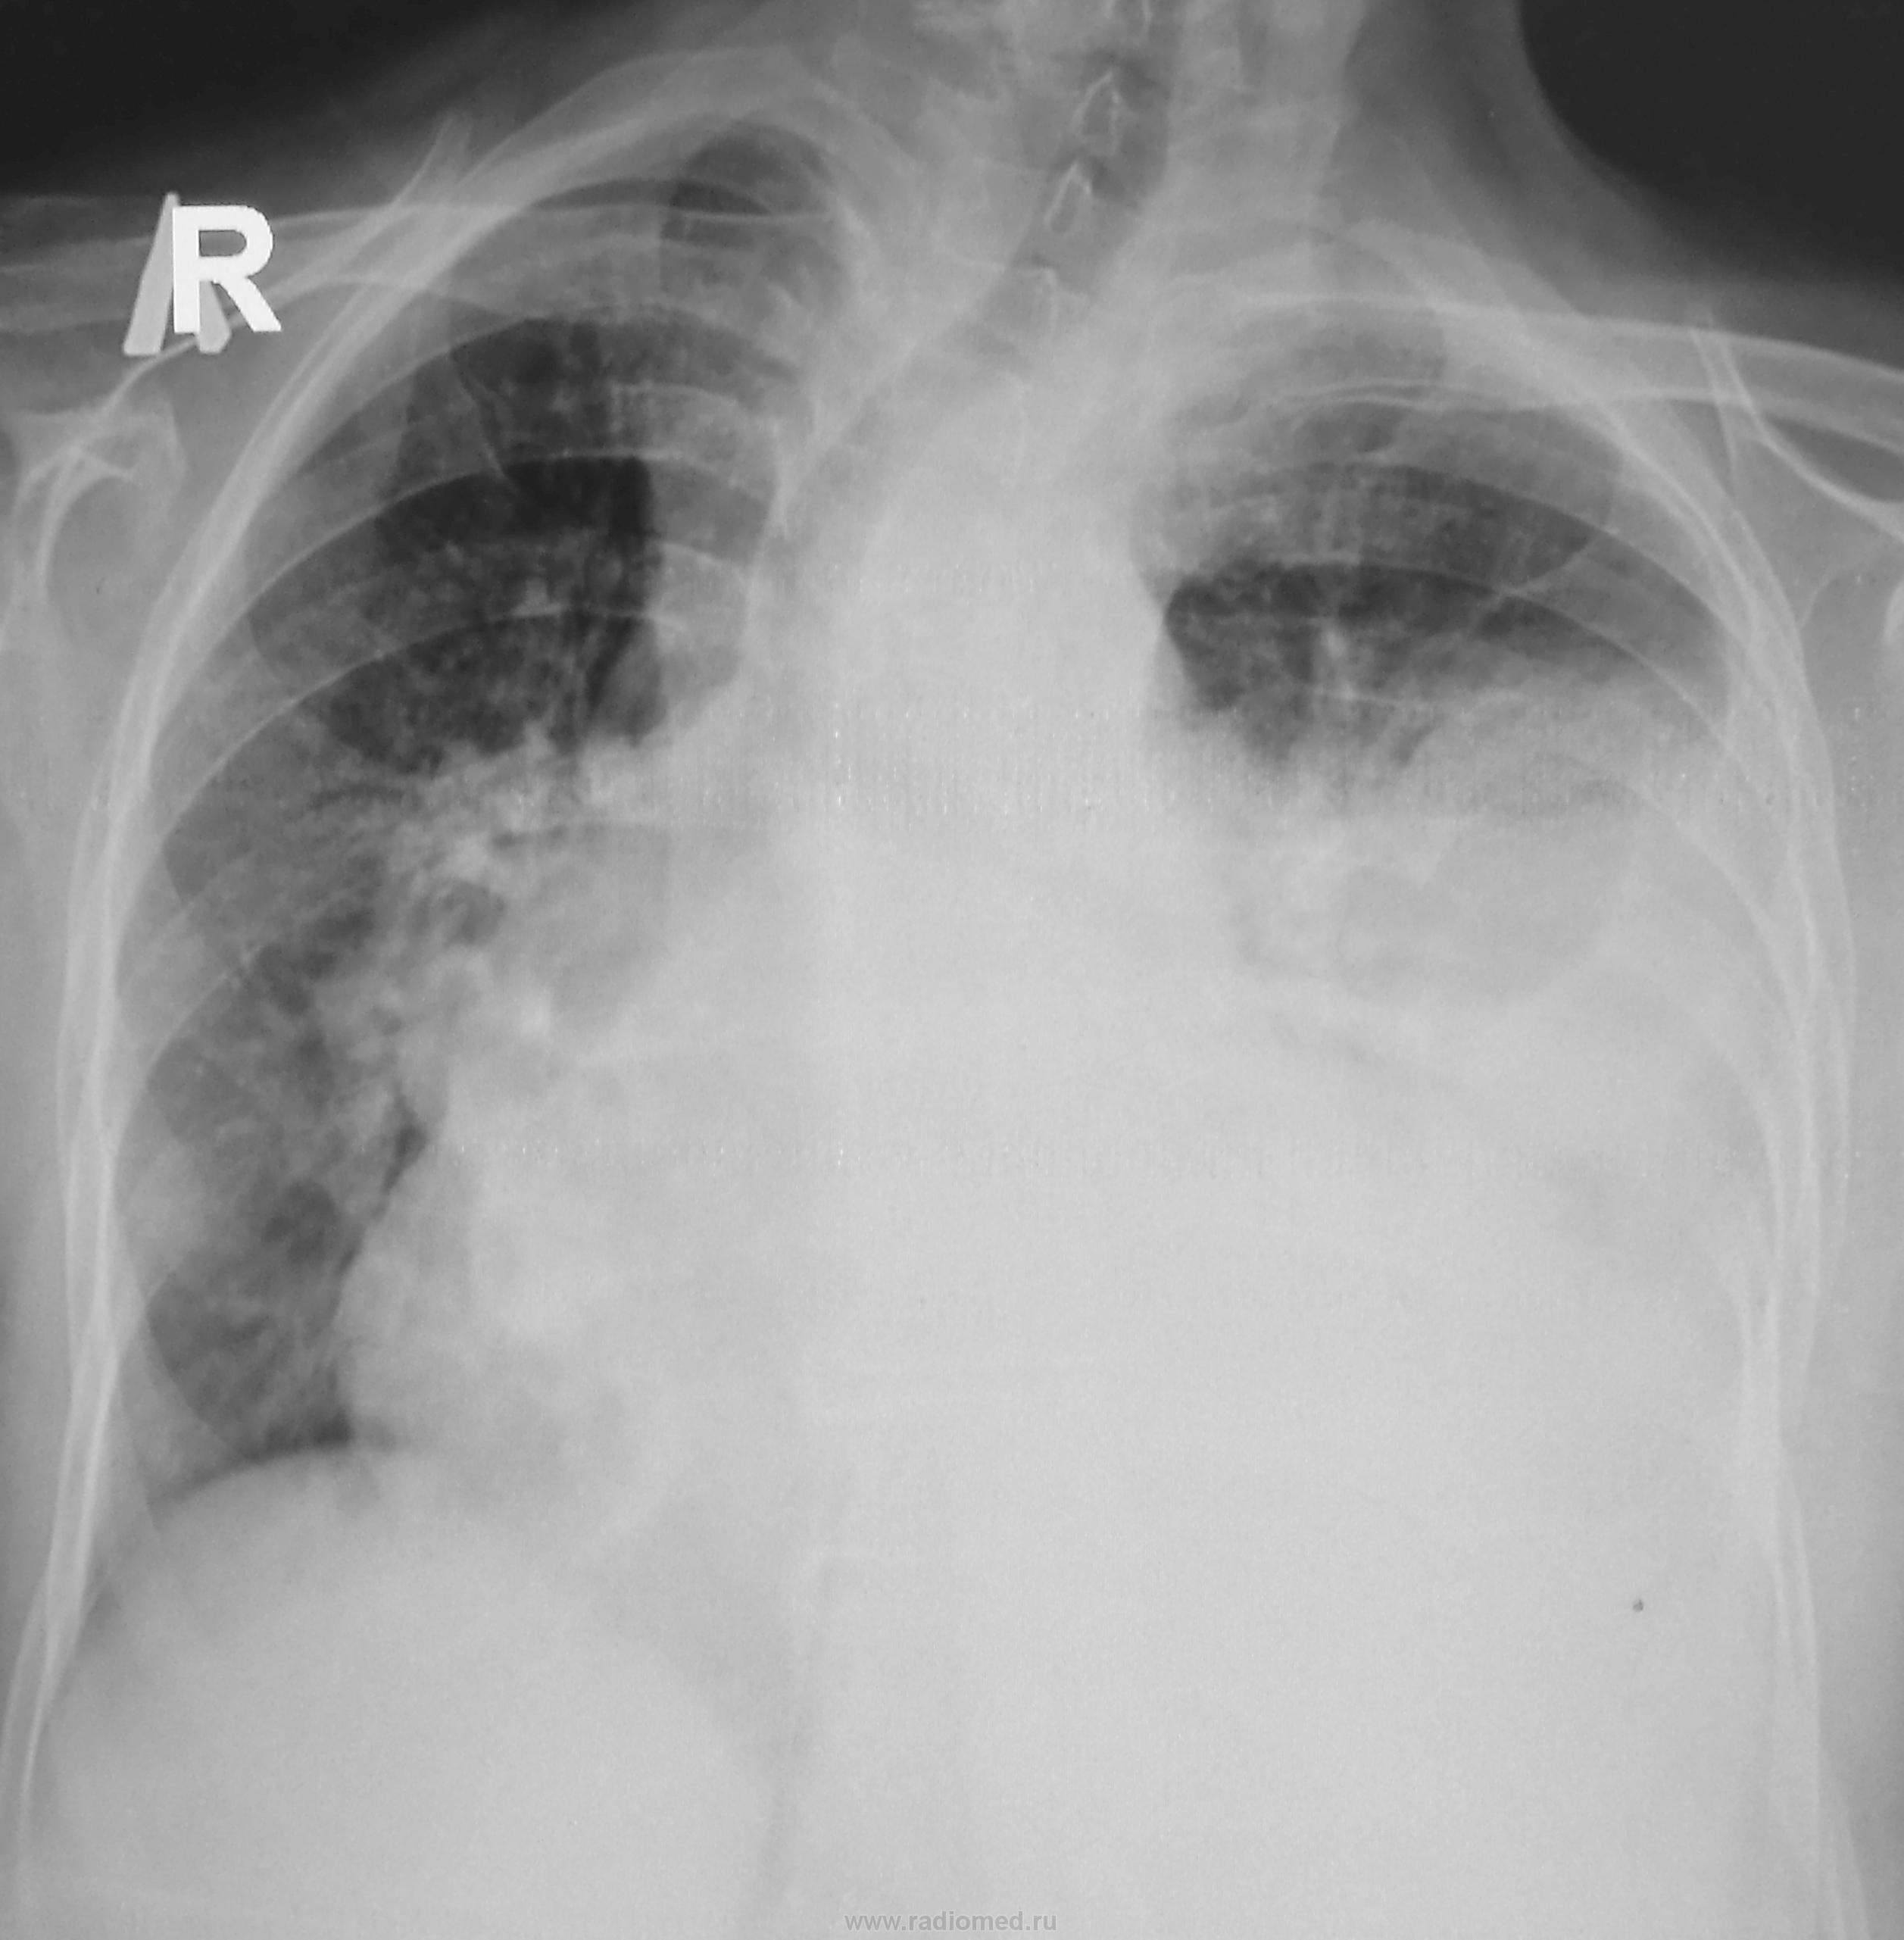

С подозрением на пневмонию направлен на рентгенографию ОГК

Расширено центральное средостение вероятно за счет лимфоузлов. Я бы подозревал метастазы не имея никаких данных по пациенту.

Возможно правый гемоторакс затемнен за счет жидкости,тень средостения резко смещена вправо,пр.корень расширен ,сердечная тень расширение,дополнительная тень вероятно сосуд?

Объемное давление в плевральной полости слева (выпот, видна косая граница в прямой проекции), оттесняющее средостение вправо(трахея наглядна). ЛГБ вроде проходим, дальше - тьма. Затенение переднего легочного пространства в боковой проекции, радиарная тяжистость инфильтрата слева, увеличение правого корня, кругляш в S9 слева на боковой - накопано богато. Вероятны дела онкологические, средостенные в легкое иль наоборот (что менее вероятно), однако мтс плеврит и в паренхиму наиболее реальны.

Я сначала тоже про жидкость подумала, но где она на боковом? Осумкованный выпот не смог бы так подвинуть средостение. Я думаю, в левом легком очень большая опухоль

Предполагал как и Вы. Но, если большая опухоль в левом легком, то где она на боковом снимке? Не напрашивается ли патология в средостении?

Признаки  центрального новообразования левого легкого, с ателектазом верхней доли, компенсаторное вздутие нижней. Динамика= уменьшению перипроцесса.